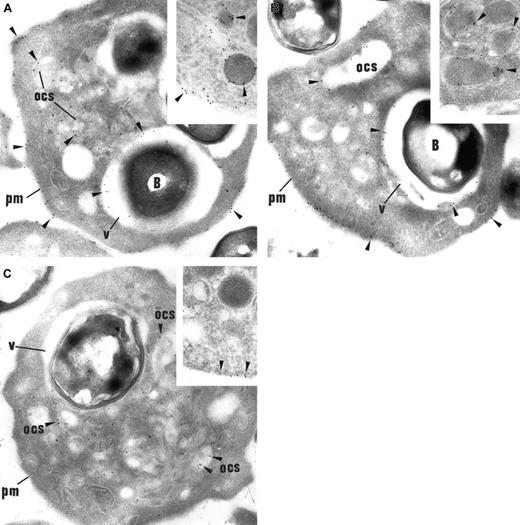

To document the antigenic composition of the limiting membrane of vacuoles that surround internalized bacteria (engulfing vacuoles), immunolabeling experiments were performed on thin sections of thrombin-activated platelets incubated with S aureus, by using antibodies against several platelet glycoproteins (αIIbβ3, P-selectin, GPIb, and fibrinogen). Within resting platelets, αIIbβ3 is present along the plasma membrane, the membrane of the OCS, and the α-granule membrane (Figure 2A, inset); P-selectin is restricted to the α-granule membrane (Figure 2B, inset); GPIb is located mainly on plasma membrane (Figure 2C, inset). During platelet activation, antigens redistribute in the following way: αIIbβ3 plasma membrane expression significantly increased and P-selectin appeared on the plasma membrane; OCS and GPIb have cleared from the plasma membrane and are internalized into the OCS membrane. In our samples, upon platelet activation, OCS membrane expressed the 3 antigens αIIbβ3, P-selectin, and GPIb.25 The limiting membrane of the engulfing vacuoles also expressed αIIbβ3 and P-selectin (Figure 2A-B), but GPIb was consistently absent from this compartment (Figure 2C). Thus, GPIb, which is expressed mainly in OCS after platelet activation, is apparently not expressed in engulfing vacuoles. These results suggest that the engulfing vacuoles exhibit a different antigenic composition from the OCS.

S aureus. (A) In platelets containing bacteria (B), αIIbβ3 labeling (arrowheads) is prominent along the plasma membrane (pm) and the OCS membrane. Like OCS, the limiting membrane of the engulfing vacuoles (v) is heavily labeled. Original magnification, × 23 250. Inset: In control platelets, αIIbβ3 is immunodetected along the plasma membrane and the α-granule membrane. Inset original magnification, × 34 100. (B) P-selectin (arrowheads) is consistently detected along the plasma membrane (pm) and the OCS, as expected, following platelet activation. The membrane of the engulfing vacuoles surrounding the bacteria is also labeled for P-selectin. Original magnification, × 23 250. Inset: In control platelets, P-selectin is restricted to the α-granular membrane and is absent from plasma membrane. Inset original magnification, × 34 100. (C) GPIb (arrowheads), which is immunodetected on the OCS membrane, is not found within the membrane of the engulfing vacuoles, showing that this compartment is distinct from the OCS. Noteworthy, GPIb is absent from the plasma membrane (pm), showing its redistribution into the OCS, a distribution pattern that is well established in activated platelets. Original magnification, × 23 250. Inset: In control platelets, GPIb is located mainly on the plasma membrane. Inset original magnification, × 34 100.